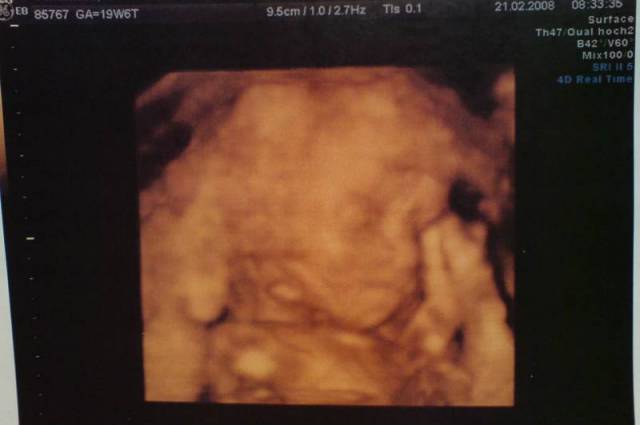

19+6 20. SSW Datum 19.05.2008 20. SSW